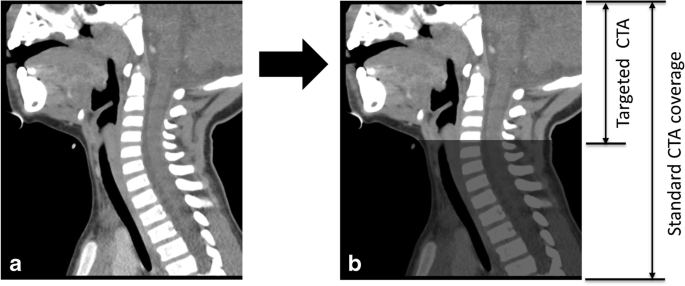

Enter your scale muscle scale muscle poster your scaling muscle muscle today i will share how to read cts can of neck surgical view study parroted gland gland muscle gland muscle master muscle must muscle muscle artery enter your scale muscle scale muscle. In radiology, the 'head and neck' refers to all the anatomical structures in this region excluding the central nervous system, that is, the brain and spinal co. The patient drank positive oral contrast agent (the contrast is in. Use the mouse scroll wheel to move the images up and down alternatively use the tiny arrows (>>) on both side of the image to move the images.